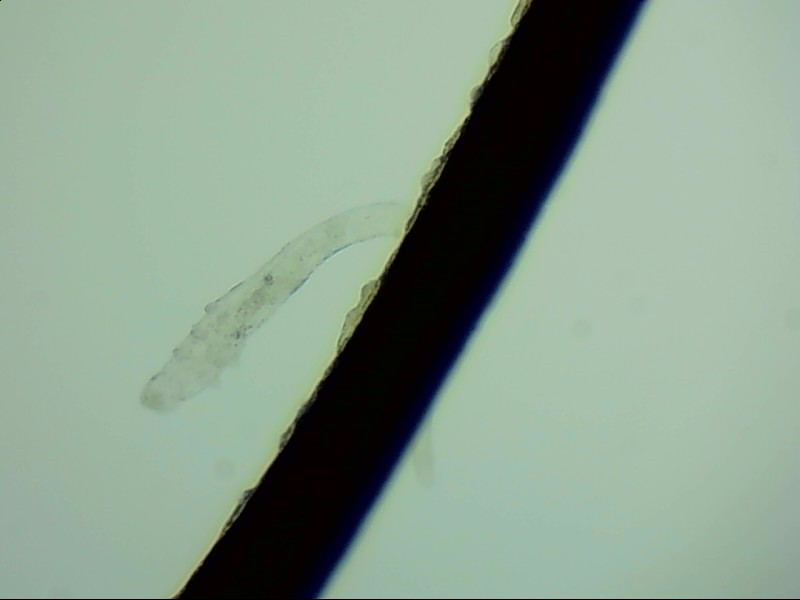

螨蟲怎么會(huì)爬到睫毛里?廈門眼科中心蠕形螨性瞼緣炎門診張麗穎博士后介紹,人體螨蟲主要有兩種,一種是皮脂螨,主要寄生于皮脂腺和瞼板腺內(nèi);另一種是蠕形螨,“住”在睫毛毛囊里,晚上從毛囊里爬出來,白天躲在毛囊里產(chǎn)卵。

據(jù)介紹,這種疾病確診主要通過觀察睫毛里的螨蟲數(shù)量聯(lián)合瞼緣及眼表情況共同診斷。一般而言,如果12根睫毛里,有2條或是超過2條的螨蟲就可以被確診。如果檢查確實(shí)發(fā)現(xiàn)較多的蠕形螨感染,建議加上抗螨治療。張麗穎說,發(fā)現(xiàn)眼睛干澀、發(fā)癢,不要自行用藥,建議到醫(yī)院就診。如果長期反復(fù)多發(fā)霰粒腫,要考慮是否存在蠕形螨感染。